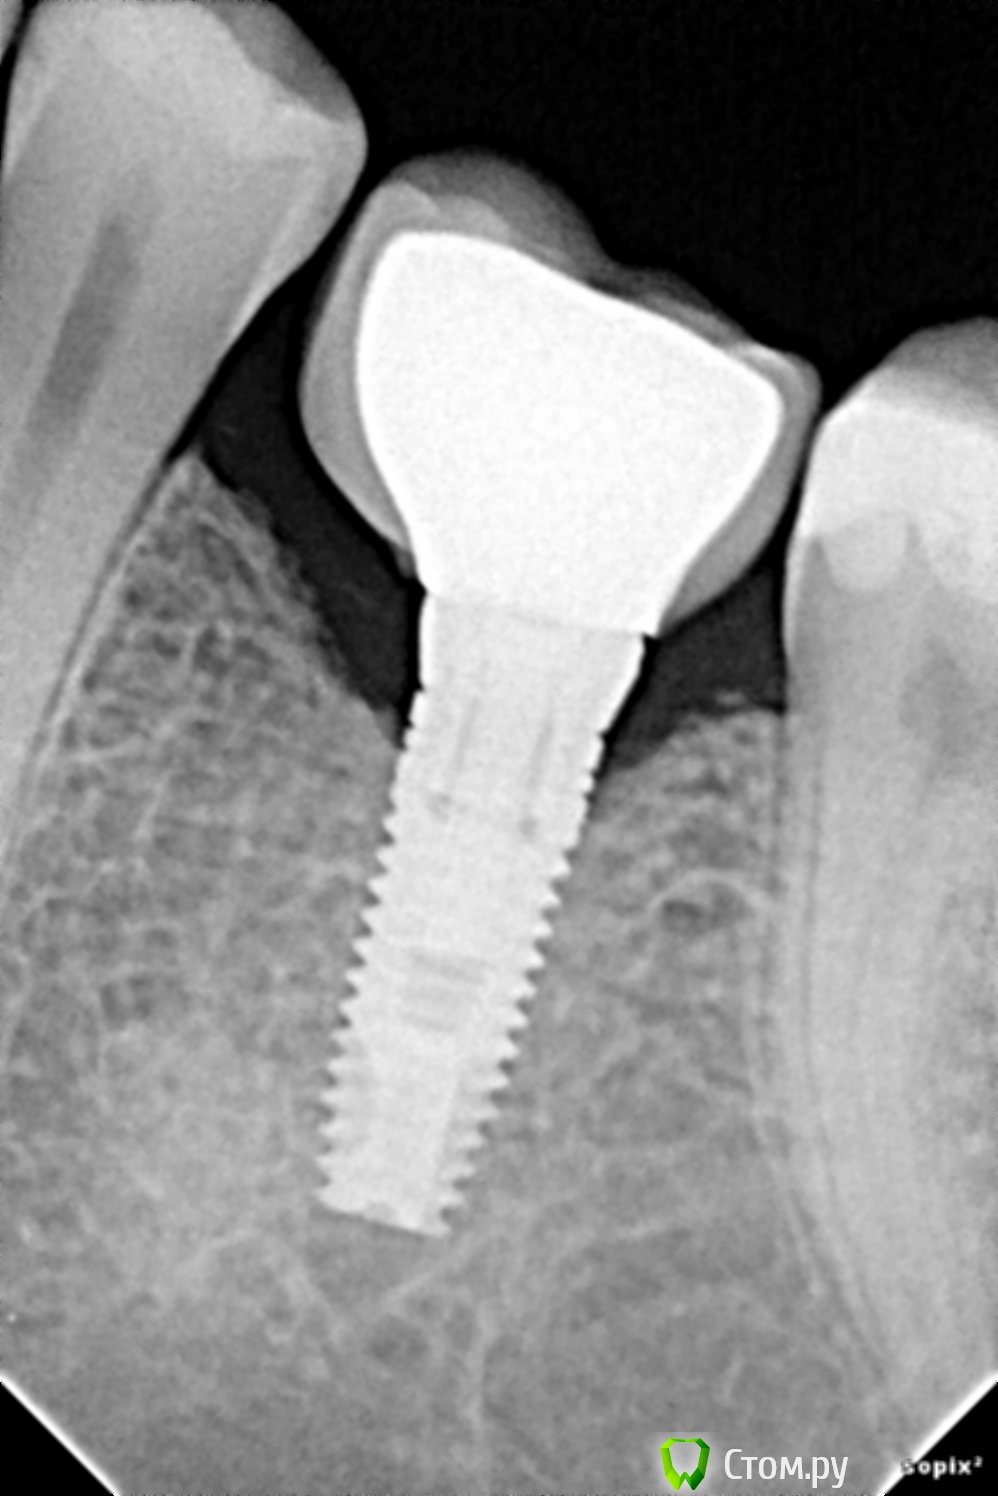

drwatson Опубликовано 28 января, 2014 Поделиться Опубликовано 28 января, 2014 Здравствуйте. 3 месяца назад мне был установлен имплант на место нижней левой 6-ки. Сразу же возникла проблема - под имплант попадает пища. Кроме того имплант сидит на десне, а не в лунке. Обратился к хирургу, его ответ: " все нормально, просто нужно вычищать". Вот снимок этого зуба. Подскажите, пожалуйста, если это, конечно, возмоно по снимку, что делать с этим зубом, т. к. не покидает ощущение, что так быть не должно. Ссылка на комментарий

drwatson Опубликовано 28 января, 2014 Автор Поделиться Опубликовано 28 января, 2014 снимок: Ссылка на комментарий

SergioS Опубликовано 28 января, 2014 Поделиться Опубликовано 28 января, 2014 ничего критичного по снимку. Остальное даст визуальный осмотр. Сходите на прием к другому доктору!Возможно действительно недостает гигиены. Пользуйтесь ирригатором. И тема больше бы пошла к ортопедическому разделу. Ссылка на комментарий